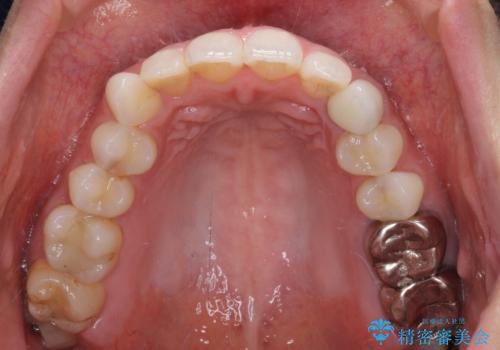

- 前歯の保険のかぶせものをセラミックに替えたいと来院された患者様です。

保険のかぶせもの特有の変色や縁の金属色、歯根が一部見えている点が気になるとのことでした。

土台の金属を除去してファイバーコアによる土台植立を行い、オールセラミッククラウンにて補綴することとしました。

前歯1本の治療では、オールセラミッククラウンといえども周囲と調和しなければ自然な仕上がりにはなりません。

今回は既製の色調のセラミックを選択されましたが、もっと色合いにこだわりたい場合には、オーダーメイドタイプのセラミッククラウンをご選択いただいています。